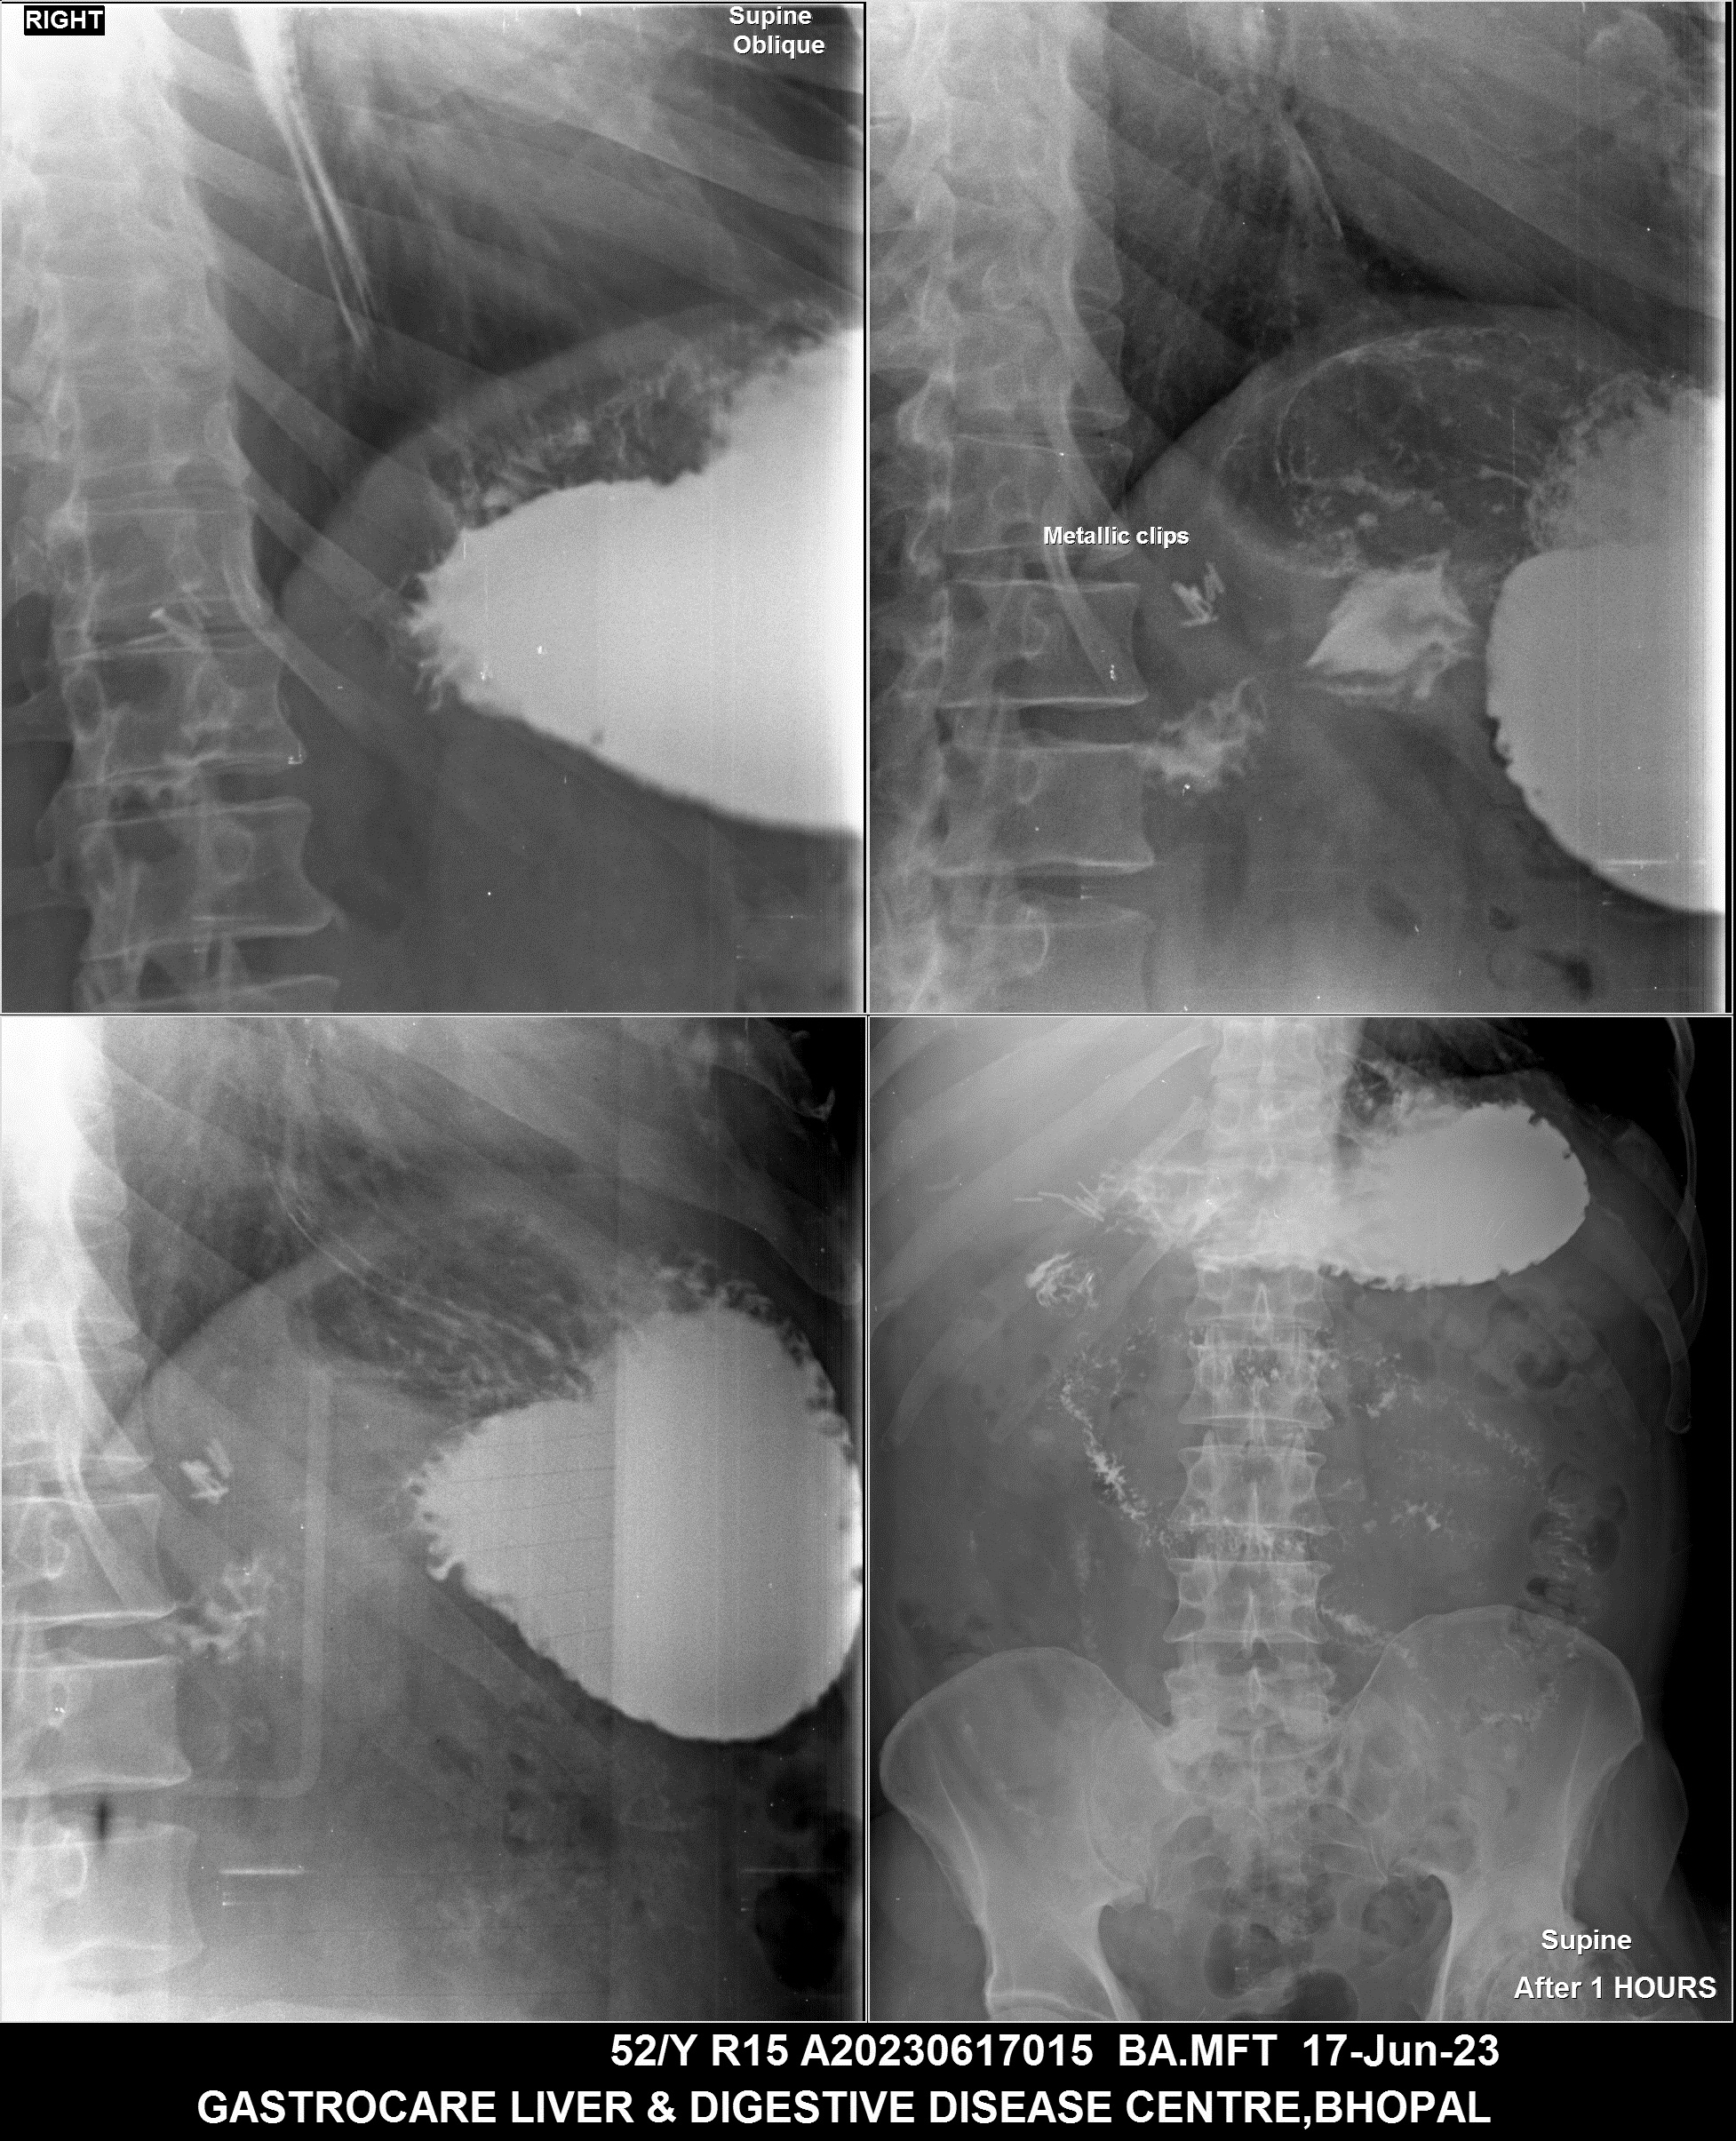

Section: BAM Total: 43 images

BaM Enteroclysis Loopogram BaE Fistulogram Urethrogram HSG